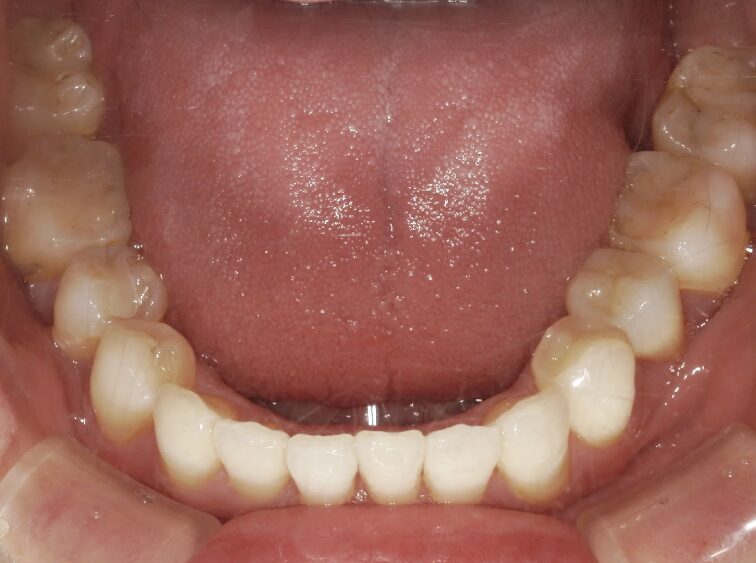

治療前

前歯が全く当たっていないを主訴に当院を受診され、開咬・上顎前突・下顎叢生を認めました。

上顎左右4番抜歯を行いIPRを使用してマウスピース型矯正装置(インビザライン)を使用し、改善を行いました。